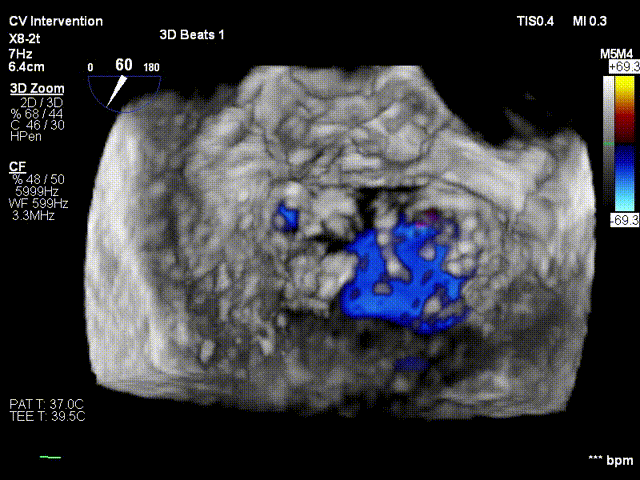

患者平卧导管床,常规消毒铺巾,呼吸机辅助呼吸,穿刺右侧股静脉,于经食道超声指导下穿刺房间隔,造影确认穿刺针位于左房后。予super stiff置入左上肺静脉。于右股静脉沿super stiff推送MitraClip Guide Catheter于左房。于经食道超声指引下,推送XTR Clip Delivery System至二尖瓣左房面,食道超声确认12点钟方向推送至二尖瓣左室面,重新调整DC handle使Clip Arm至11点钟方向。顺利捕捉二尖瓣前叶A3及后叶P3区域,Grap down后夹闭Clip Arm。经食道超声评估二尖瓣返流由MR4+减少至微量,确认前叶有效夹持长度13mm,后叶有效夹持长度为11mm,确认瓣叶夹持牢固,释放瓣膜夹。经食道超声再次评估二尖瓣返流微量,二尖瓣压差1mmHg,退出MirtaClip系统,3DTEE评估房间隔 穿刺口少量左向右分流,未见右向左分流,未见心包积液,结束手术。

患者平卧导管床,常规消毒铺巾,呼吸机辅助呼吸,穿刺右侧股静脉,于经食道超声指导下穿刺房间隔,确认穿刺针位于左房后交换房间隔穿刺导管至左房, 再予super stiff置入左上肺静脉;退出房间隔导管后予16F预扩张鞘扩张右股静脉;于右股静脉沿Super stiff推送24F MitraClip steerable Guide Catheter于左房, 于3DTEE指导下,推送NTR Clip Delivery System至二尖瓣左房面,3DTEE确认12点钟 方向推送至二尖瓣左室面,重新调整DC handle使Clip Arm至11点钟方向。顺利捕捉 二尖瓣前叶A1及后叶P1区域,Gripper down后夹闭Clip Arm,3DTEE评估二尖瓣反流 由MR4+减少至1+,确认A1有效夹持长度8mm,P1有效夹持长度8mm,确认瓣叶夹持牢固, 释放瓣膜夹,3DTEE再次评估二尖瓣反流1+;退出MitraClip系统,3DTEE评估房间隔 穿刺口少量左向右分流,3DTEE评估房间隔 穿刺口少量左向右分流,未见右向左分流,未见心包积液,结束手术。